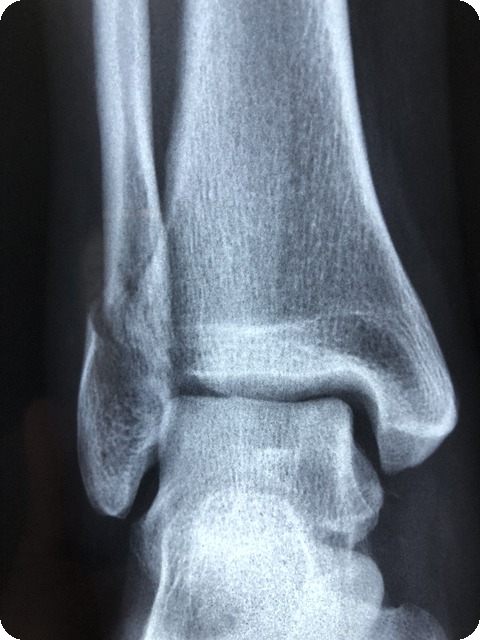

발목 염좌는 일반적으로 발목 관절을 지탱하는 인대가 외부의 힘에 의해 늘어나거나 찢어지는 부상을 의미합니다. 발목 주변의 인대는 뼈와 뼈를 연결하여 관절의 안정성을 유지하는 역할을 합니다. 발목이 비정상적으로 꺾이거나 돌아갈 때, 이러한 인대에 과도한 스트레스가 가해져 염좌가 발생하게 됩니다.

의학적으로는 발목 염좌가 발목 관절의 인대에 손상이 발생하며, 보통 외측 인대인 전거비인대, 종비인대, 후거비인대 중 하나 이상이 손상되는 상태를 의미합니다.